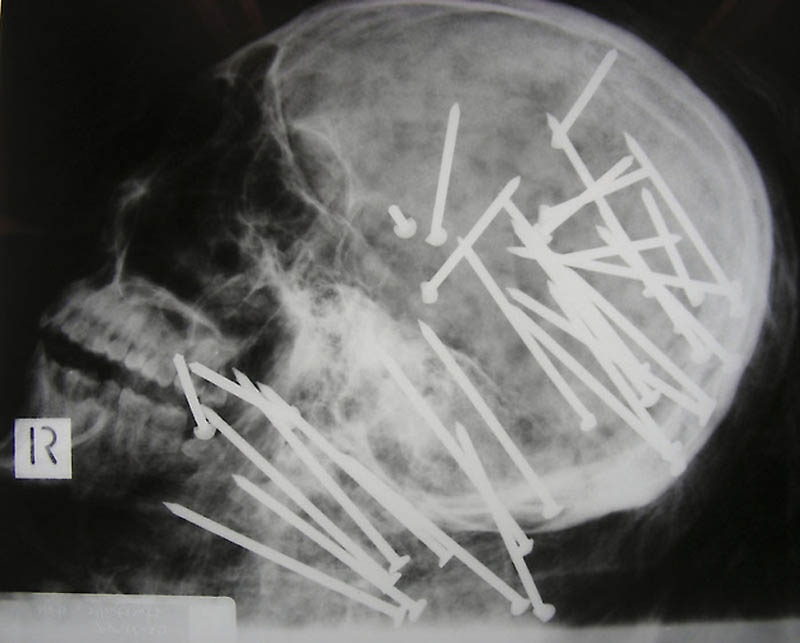

Череп китайца, которому в голову выстрелили пневматическим молотком.